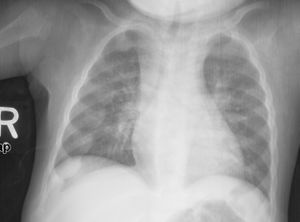

Chest X ray showing changes consistent with rickets, this changed is usually referred to as Rosary beads of rickets - نقص كالسيوم الدم (انخفاض مستويات الكالسيوم بالدم)

تجس عقيدات كحبات السبحة ناجمة عن تضخم الغضاريف في مناطق الوصل القصي الضلعي، وقد تكون مرئية للعين أيضاً. يتبارز القص إلى الأمام ويسبب تشوهاً (صدر الحمامة) كما يحدث انخفاض للداخل على طول الحافة السفلية للأضلاع يدعى بتثلم هاريسون مع غؤور الحفرة الخنجرية (أسفل القص).